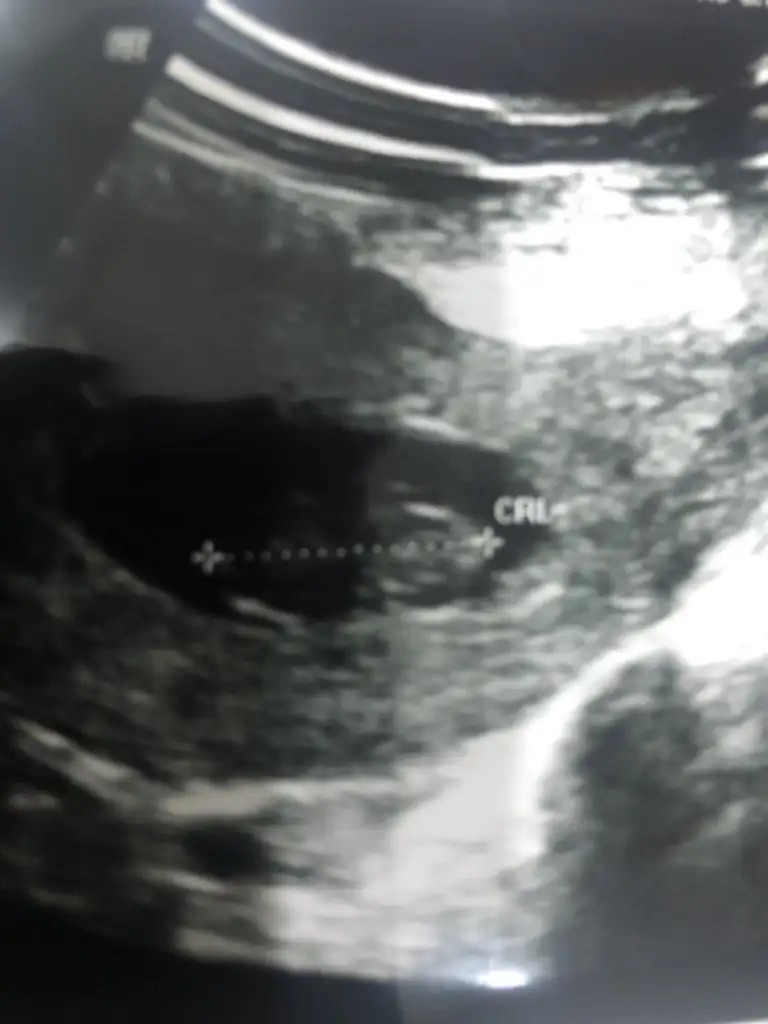

Ikra meyracim bugün dr a gittik, dr %100 kiz dedi. Bildiniz valla, teşekkür ediyorum, Allah herkese gönlünden geçeni sağlıkla nasip etsin inşKız gibi geldi nubu banaumarım gonlunuzdeki olsun inşallahEki Görüntüle 2748350

Sağlıkla gelsin prensesIkra meyracim bugün dr a gittik, dr %100 kiz dedi. Bildiniz valla, teşekkür ediyorum, Allah herkese gönlünden geçeni sağlıkla nasip etsin inş